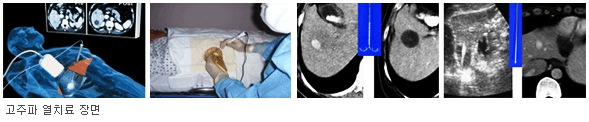

고주파 열치료법

영상의학과에서 간암 치료에 직접 관여하는 것으로 고주파열치료와 경동맥 화학색전술이 있습니다. 특히, 우리 병원의경우 고주파열치료를 국내에 가장 먼저 도입하고 현재까지 가장 많은 시술을 하였습니다. 고주파열치료는 간암에 대해 초음파를 보면서 직접 바늘을 찔러 바늘 끝에서 발생한 고주파가 주변 간암 조직의 이온을 뒤흔들고 이때 발생한 마찰열이 간암 조직을 태워 죽이는 원리입니다.

고주파열치료 과정

고주파열치료는 대개 오후에 시행하는데, 다음 날 오전 중으로 1차 치료성공과 합병증을 확인한 후 퇴원시키고 있습니다.

고주파열치료 성적

과거에 다른 치료 없이 첫 발견되어 고주파열치료로 치료 받은 간세포암 462개를 분석한 결과 1차 치료성공률은 97%, 국소 재발률은 12%, 국소 완치률은 84%, 중요 합병증 발생율은 4%, 전체 환자들의 1년 생존률은 97%, 3년 생존률은 76%, 5년 생존률은 58%로 분석되었습니다. 또한, 고주파열치료 후 한 번도 간암 재발없이 살고 있는 1년 무병 생존률은 70%, 3년 무병 생존률은 29%, 5년 무병 생존률은 20%로 조사 되었습니다. 이러한 결과들은 간절제 수술 결과를 추적하는 좋은 결과입니다.

▲ 고주파 열치료 치료전부터 치료 종료 후 5분까지